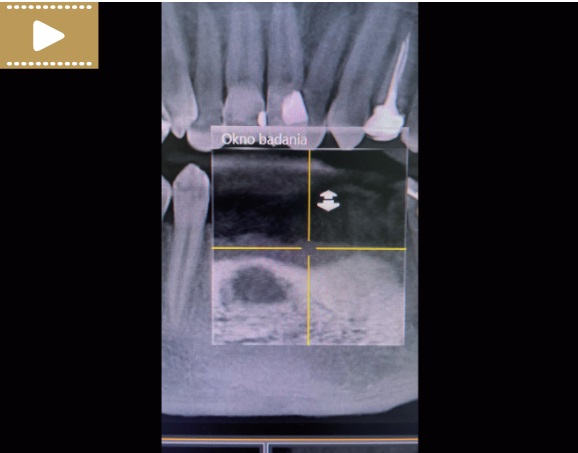

Film 1. CBCT przed rozpoczęciem leczenia endodontycznego zębów 31 i 41, płaszczyzna czołowa (kwiecień 2021 r.).